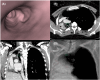

Endobronchial tuberculosis (EBTB) presents significant clinical challenges, particularly when complete bronchial obstruction occurs. In this case, a young woman with right main bronchus occlusion due to tuberculosis (TB) was treated using a novel approach. Instead of using a traditional rigid bronchoscope, a flexible approach was adopted. Under precise fluoroscopic guidance, a 21-gauge transbronchial aspiration needle was used to puncture the obstruction, allowing passage of the guidewire and subsequent balloon dilation. The use of virtual bronchoscopy, developed using computed tomography scans, ensures safe navigation around critical vascular structures. Postoperatively, the patient showed significant symptomatic improvement without complications. This innovative approach not only demonstrates the efficacy and safety of using biopsy needles and virtual bronchoscopy for managing complete bronchial obstructions in EBTB but also opens the door for future innovative solutions in such complex cases.